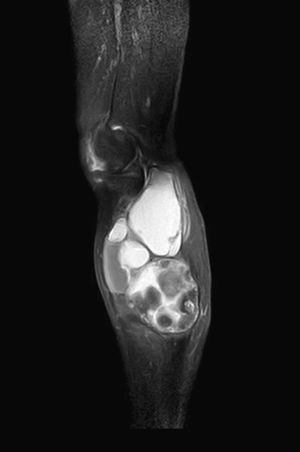

We present the case of an 83-year-old male patient with osteoarthritis, who came to the emergency room due to acute inflammation of the leg simulating DVT. On physical examination, there was a mass of elastic consistency, non-pulsatile, painful, in the popliteal fossa, extending to the leg (Fig. 1). The differential diagnosis was made with Baker cyst. The patient underwent, as a technique of choice, an ultrasound. The color Doppler mode showed patency of the deep venous system. Musculoskeletal ultrasound evidenced a well-defined collection, adjacent to the medial gastrocnemius muscle belly, full of vague echoes predominantly of low amplitude (Fig. 2) Despite being frequent, the size of the tumor made ultrasound insufficient and we decided to perform specific knee MRI with T1 potentiated sequences, T2* sequences (Figs. 3–5) and, after administration of intravenous contrast, we confirmed the existence of giant popliteal cyst of 17cm×9cm. The patient was treated conservatively, using, in the first place, nonsteroidal anti-inflammatory drugs, with clinical improvement and asymptomatic after the first 6 months. For this reason, along with the age of the patient and in spite of the cyst barely changing its size, surgical treatment has so far been dismissed.